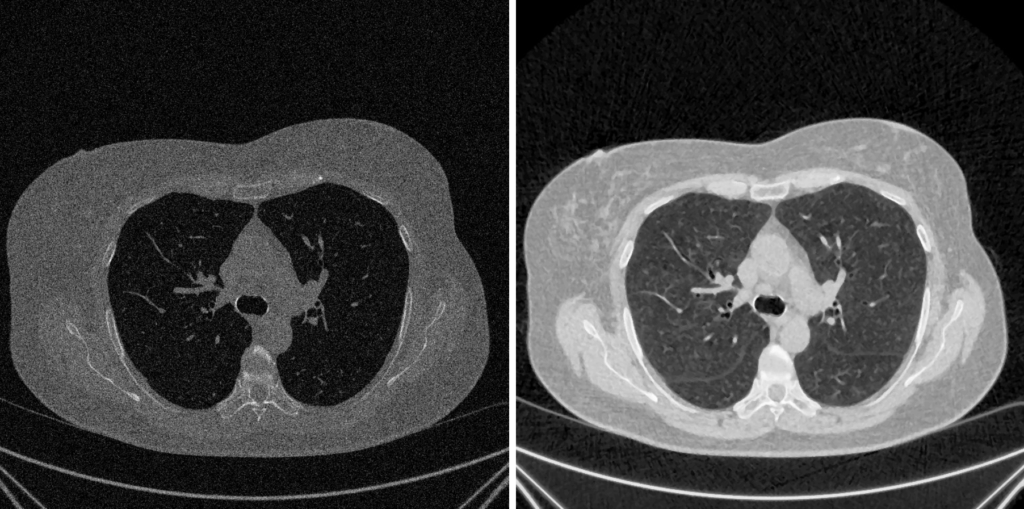

Equalizzazione Adattativa dell’Istogramma (CLAHE)

CLAHE rappresenta la soluzione “intelligente” e all’avanguardia per superare i limiti dell’equalizzazione globale, affermandosi come lo standard de-facto nell’imaging medicale.

Principio Fondamentale

A differenza dei metodi che analizzano l’istogramma complessivo, CLAHE opera localmente. Migliora il contrasto solo nelle aree necessarie, evitando al contempo l’amplificazione del rumore di fondo.

Processo Operativo (I 5 Passaggi)

- Suddivisione in Tessere (Tile Generation): L’immagine viene inizialmente suddivisa in una griglia di blocchi regionali di piccole dimensioni (le “tessere,” ad esempio 8×8).

- Calcolo degli Istogrammi Locali: Per ciascuna tessera viene calcolato un istogramma indipendente.

- Clipping dell’Istogramma (Il “CL” di CLAHE): Questa fase cruciale impone un “limite” (il Clip Limit). Qualsiasi livello di grigio (bin) che superi tale limite, spesso a causa della presenza di rumore, viene “tagliato.” L’eccesso risultante viene poi ridistribuito uniformemente sugli altri bin. Questo meccanismo previene efficacemente la sovra-amplificazione del rumore.

- Equalizzazione Adattiva: Viene applicata la classica equalizzazione (basata sulla funzione di distribuzione cumulativa – CDF) a ciascun istogramma locale che è stato “clippato.”

- Interpolazione per Fluidità: Per eliminare l’effetto visivo “a scacchiera” derivante dalla divisione in tessere, i valori finali dei pixel vengono calcolati tramite interpolazione bilineare tra le mappature delle tessere adiacenti, garantendo una transizione cromatica fluida e omogenea.